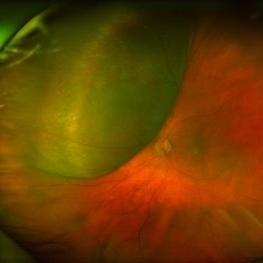

Large, Dome-Shaped Peripheral Choroidal Melanoma - Widefield Color

Large, Dome-Shaped Peripheral Choroidal Melanoma - Widefield Color

Feb 13 2020 by Michael Seider, MD

Large, dome-shaped peripheral choroidal melanoma of the left eye with inferior exudative retinal detachment. Note the lack of obvious orange pigment over the tumor and apparent drusen anteriorly. A lack of ophthalmoscopically obvious lipofuscin is not uncommon among larger choroidal melanomas. B-Scan ultrasonography (transverse, 10 o’clock) confirms a low-moderate internally reflective dome-shaped choroidal lesion with a small adjacent retinal detachment. Ultrasound biomicroscopy (radial, 10 o’clock) confirms no ciliary body involvement of the tumor.

Large, Dome-Shaped Peripheral Choroidal Melanoma - B Scan

Large, Dome-Shaped Peripheral Choroidal Melanoma - B Scan

Feb 13 2020 by Michael Seider, MD

Large, dome-shaped peripheral choroidal melanoma of the left eye with inferior exudative retinal detachment. Note the lack of obvious orange pigment over the tumor and apparent drusen anteriorly. A lack of ophthalmoscopically obvious lipofuscin is not uncommon among larger choroidal melanomas. B-Scan ultrasonography (transverse, 10 o’clock) confirms a low-moderate internally reflective dome-shaped choroidal lesion with a small adjacent retinal detachment. Ultrasound biomicroscopy (radial, 10 o’clock) confirms no ciliary body involvement of the tumor.

Large, Dome-Shaped Peripheral Choroidal Melanoma - UBM

Large, Dome-Shaped Peripheral Choroidal Melanoma - UBM

Feb 13 2020 by Michael Seider, MD

Large, dome-shaped peripheral choroidal melanoma of the left eye with inferior exudative retinal detachment. Note the lack of obvious orange pigment over the tumor and apparent drusen anteriorly. A lack of ophthalmoscopically obvious lipofuscin is not uncommon among larger choroidal melanomas. B-Scan ultrasonography (transverse, 10 o’clock) confirms a low-moderate internally reflective dome-shaped choroidal lesion with a small adjacent retinal detachment. Ultrasound biomicroscopy (radial, 10 o’clock) confirms no ciliary body involvement of the tumor.